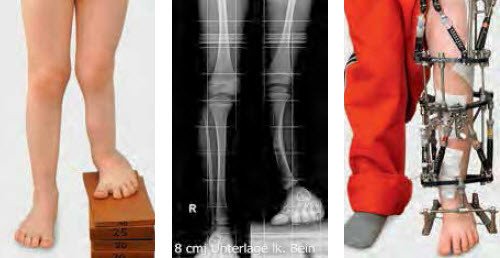

Liegen stabile Gelenkverhältnisse vor, kann mit dem Ausgleich vorliegender Beinlängendifferenzen und der Korrektur von Achsenfehlstellungen begonnen werden. Für Knochenverlängerungen und simultane Korrekturen von Fehlstellungen verwenden wir seit zehn Jahren den «Taylor Spatial Frame» (TSF), einen modifizierten Ringfixateur, der computergestützt simultane Korrekturen in allen Ebenen des Raums ermöglicht (Abb. 6–15).

Die Anwendung ist computergestützt und erleichtert dem Arzt die Arbeit bei der Vorbereitung, im Operationssaal und in der Nachbetreuung. Ein ausgedruckter Drehplan hilft zudem dem Patienten bei der selbstständigen Korrektur, was seine Motivation und damit auch die Compliance steigert. Ab einem Lebensalter von etwa fünf bis sechs Jahren und einem Längendefizit von 5 cm sehen wir eine Indikation zum Verlängerungseingriff. Von Verlängerungen über 5 cm bei den angeborenen Längendefiziten raten wir grundsätzlich ab, da weder vonseiten des Knochens noch in den Gelenken und Weichteilen normale Verhältnisse vorliegen. In der Regel wird die erste Verlängerung an dem am stärksten verkürzten Knochen begonnen. Bei Oberschenkelverlängerungen muss auf die Hüftsituation (Hüftdysplasie) und Kniesituation (fehlende Kreuzbänder) geachtet werden, um Luxationen dieser Gelenke zu vermeiden. In vielen Fällen wird das Kniegelenk in den externen Fixateur mit eingegliedert. Gleichzeitig zur eigentlichen Verlängerung des Knochens werden häufig schwere Achsen- und Rotationsfehlstellungen mit korrigiert.

Intraoperativ wird der Ringfixateur von aussen mit Schrauben und Drähten am Knochen befestigt. Anschliessend wird der Knochen minimal-invasiv mit einer speziellen Technik durchtrennt. Nach sieben bis zehn Tagen wird mit der graduellen Knochenverlängerung begonnen. Die Verlängerungsgeschwindigkeit beträgt etwa 1mm pro Tag, damit eine Nachreifung des verlängerten Knochens stets möglich ist (Abb.12–14). Nach Abschluss der Verlängerung muss der Fixateur am Bein bleiben, bis der verlängerte Knochen ausgereift und belastungsstabil ist. Üblicherweise beträgt die gesamte Tragedauer des Fixateurs etwa 30 bis 40 Tage pro verlängerten Zentimeter. Somit ist eine 6-monatige Tragedauer des Fixateurs für eine Verlängerung von 4 cm durchaus die Regel.